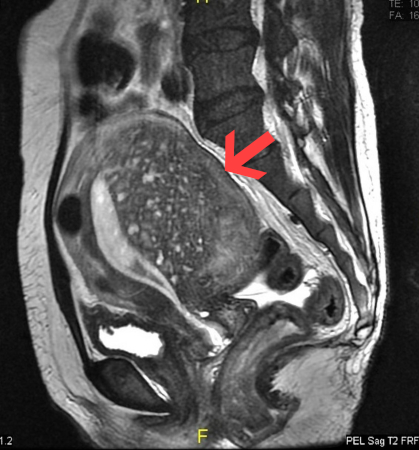

[Figure caption and citation for the preceding image starts]: Sagittal MRI of a woman's pelvis showing a uterus with adenomyosis in the posterior wall. Gross enlargement of the posterior wall is noted, with many foci of hyperintensity​Case courtesy of Dr Varun Babu, Radiopaedia.org. From the case rID: 43504; reproduced under the Creative Commons CC BY-SA 4.0 license (https://creativecommons.org/licenses/by-sa/4.0/ ) [Citation ends].com.bmj.content.model.Caption@647a130b

MRI can be used to diagnose adenomyosis by evaluating the thickness of the junctional zone, which appears as a distinct T2 hypointense band separating the T2-hyperintense endometrium and the intermediate-intensity myometrium.[69] T2 hypointense junctional zone thickness greater than 12 mm is indicative of adenomyosis, while a thickness less than 8 mm excludes the disease.[70] T2 hyperintense foci can be observed, representing cystic dilation of the endometrial glands, and are similar to anechoic myometrial cysts seen on TVUS.[63][71] T1 signal hyperintensity can be seen if haemorrhage occurs in these foci, which has high specificity (up to 95%) for adenomyosis.[63][71]

Direct features of adenomyosis that may be seen on MRI include myometrial cysts (sensitivity of 60% and specificity of 96%), adenomyoma (a myometrial mass that does not involve the uterine serosa or junctional zone), and/or external adenomyosis (involvement of the serosa but not the junctional zone).[72][73]

distinct T2 hypointense band separating the T2-hyperintense endometrium and the intermediate-intensity myometrium; T2 hypointense junctional zone thickness >12 mm is indicative of adenomyosis; T2 hyperintense foci may be observed, with or without T1 signal hyperintensity